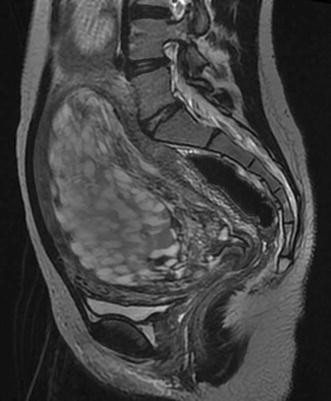

Hydatidiform Mole Mri

Complete hydatidiform mole | Radiology Reference Article | Radiopaedia.org Invasive mole | Radiology Reference Article | Radiopaedia.org Molar pregnancy | Radiology Reference Article | Radiopaedia.org Molar pregnancy | Radiology Reference Article | Radiopaedia.org | Hydatidiform Mole Mri